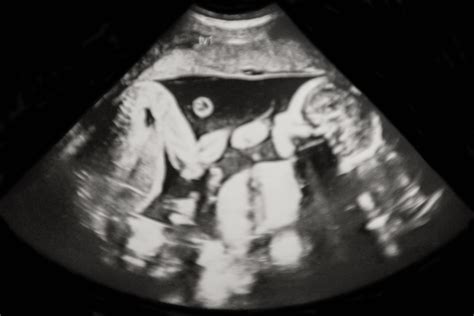

Napjainkban, az ultrahangos vizsgálatoknak köszönhetően, döbbenetes adatok derültek ki a terhességek korai szakaszáról. Kiderült, hogy a terhességek jelentős része, mintegy 8-10%-a ikerterhességként indul, ám ezeknek csupán egy kis töredéke, körülbelül 1%-a végződik ikrek születésével. A mesterséges megtermékenyítési eljárások tovább növelik az ikerterhességek arányát, ezzel együtt pedig az "elveszett iker szindróma" kockázatát is. Ez azt jelenti, hogy statisztikailag legalább minden nyolcadik ember osztozott valaha ikertestvérével az anyaméhen, de végül egyedül jött a világra.